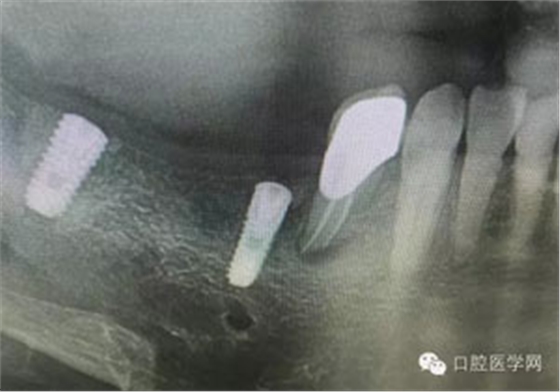

病例1:患者迫切希望保留自己的這一顆牙齒,根尖周陰影比較大,二度松動(dòng).而且旁邊有種植修復(fù)體,和患者溝通好后,治療好后觀察一個(gè)月后冠修復(fù),因?yàn)橛蟹N植的后期修復(fù),所以有了機(jī)會(huì)觀察,術(shù)后三個(gè)月和術(shù)后四個(gè)月,根尖恢復(fù)的還算不錯(cuò),希望能夠繼續(xù)觀察下去.這樣子的病例,做的時(shí)候我們一定要非常的小心,和患者要有充分的溝通以及不同科室的溝通然后決定怎么樣做比較好,假如就是出現(xiàn)了問(wèn)題,到時(shí)候我們也比較好處理些,免得我們自己到時(shí)候不好收?qǐng)觥?/span> 病例2:364647中齲的樹(shù)脂充填,現(xiàn)在樹(shù)脂的充填材料非常之多,有些時(shí)候,我們感覺(jué)有了好的材料我們就可以做出好的修復(fù),可是這是在我們有扎實(shí)的基本功的基礎(chǔ)上的,我們可以沒(méi)有那么好的樹(shù)脂,那么多的顏色選擇,修復(fù)的那么的逼真,但是我們至少要恢復(fù)患者牙齒的功能,將腐質(zhì)去除干凈,薄壁弱尖消除掉,選擇好適應(yīng)癥,給患者以盡可能好的修復(fù)。 來(lái)源于KQ88